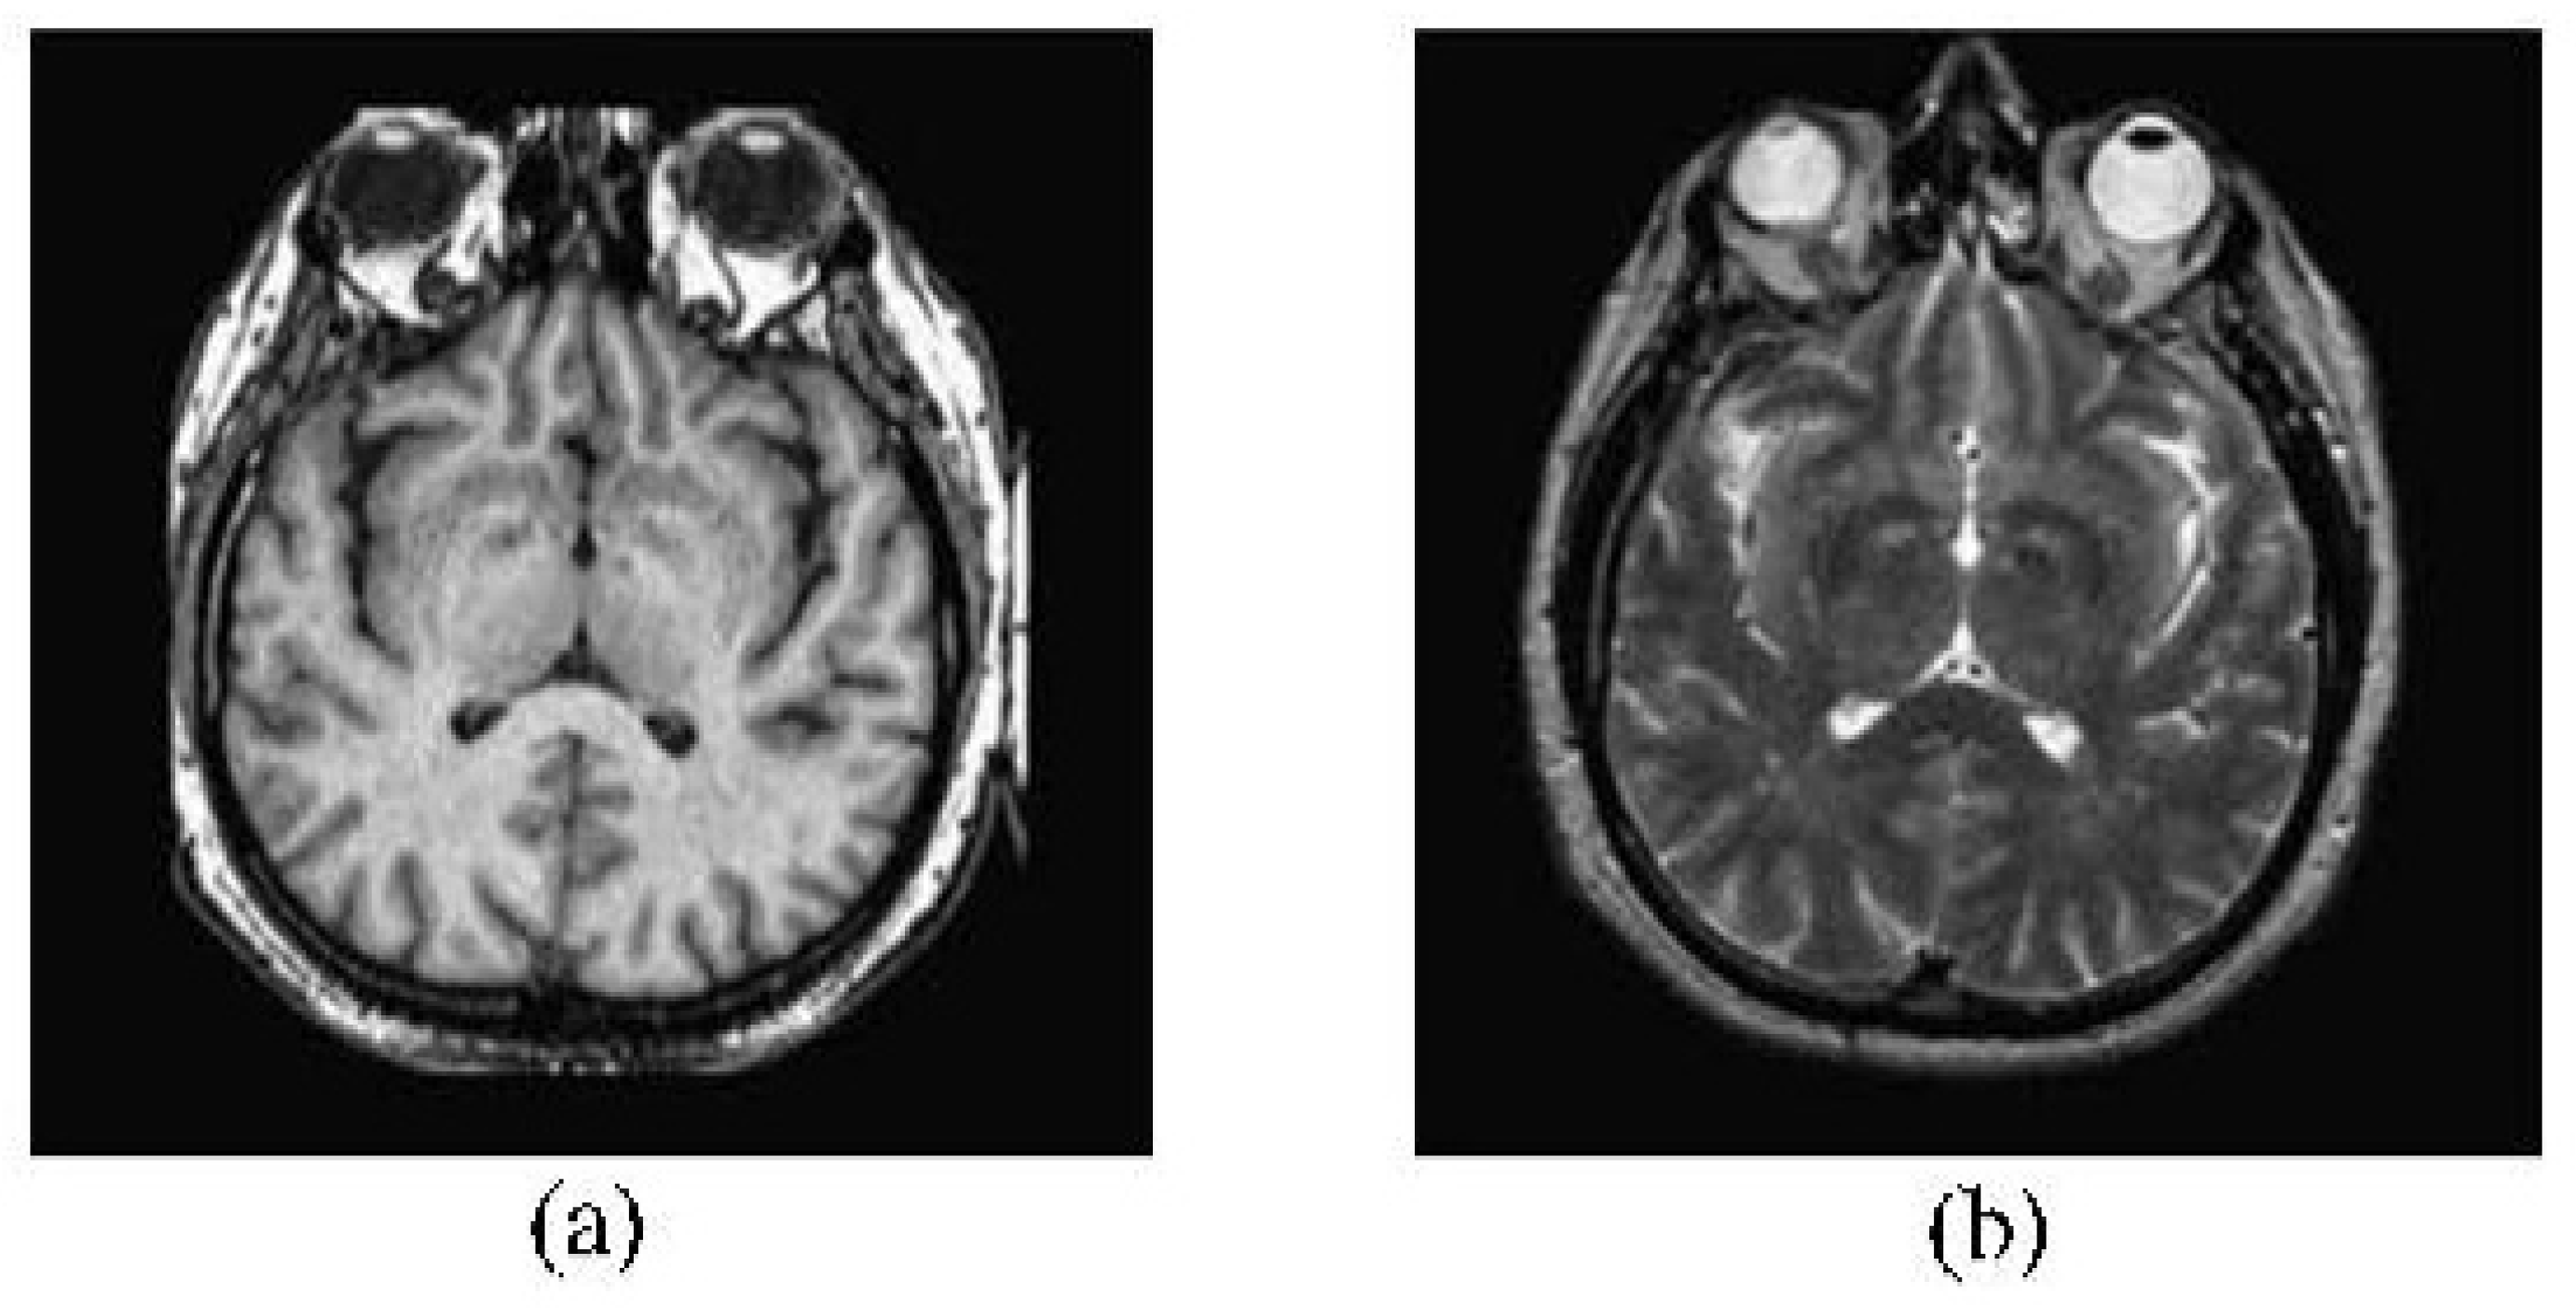

2.3. Medical Image Fusion

2.4. CT and MRI Images Fusion

2.5. MRI and PET Image Fusion

2.6. MRI and SPECT Image Fusion